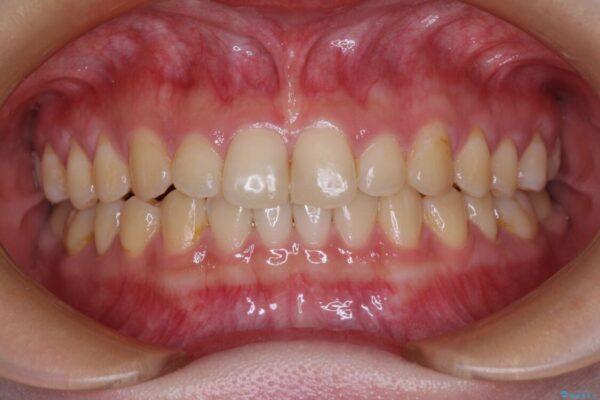

治療前

• 治療途中の奥歯と矯正治療の後戻り インビザライン・ライトによる矯正治療 治療前画像